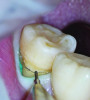

Once the cord was packed circumferentially, an additional line was marked along the previously identified finish line to provide an accurate visual reference for the tooth preparation (Figure 2). Four-handed dentistry was utilized during preparation, with the dental assistant passing hand instruments to and minimizing hand strain on the clinician. This helps enable smooth preparation from various angles while facilitating maximum control over the magnified operating field.

Fig 2. After retraction cord was packed all around the tooth under the microscope, the previous margin marks were refreshed for accurate orientation of the preparation.

Figure 2